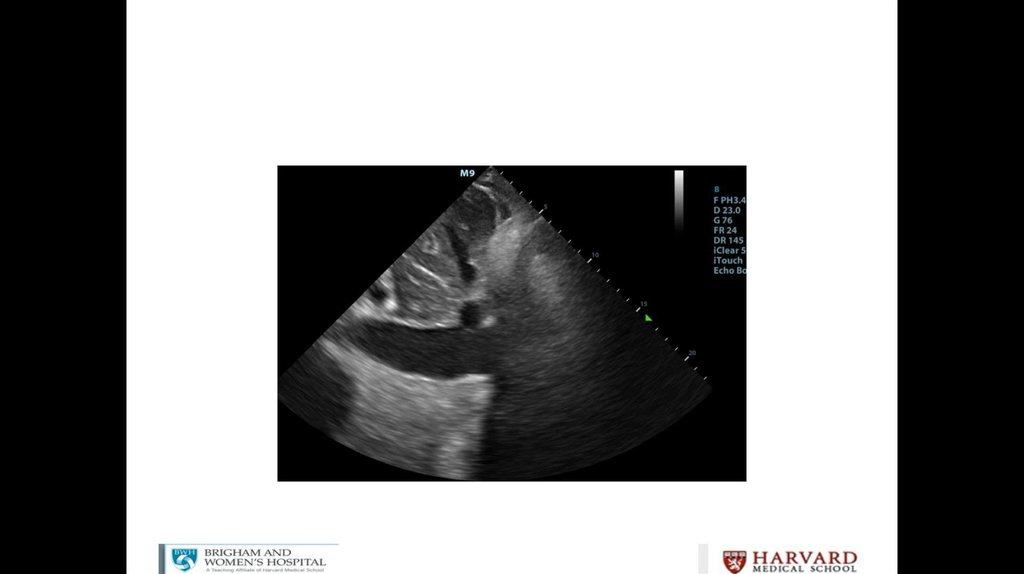

Litrasound in the ICU: What Every Intensivist Should Know